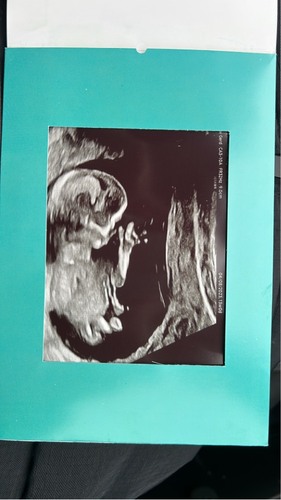

Had hem al geplaatst maar kan hem nergens terug vinden ❤️of 💙 echo is van gisteren met 16+6

Had hem al geplaatst maar kan hem nergens terug vinden ❤️of 💙 echo is van ...

Denk 💙. Had je nog een foto toevallig van eerdere echo misschien?